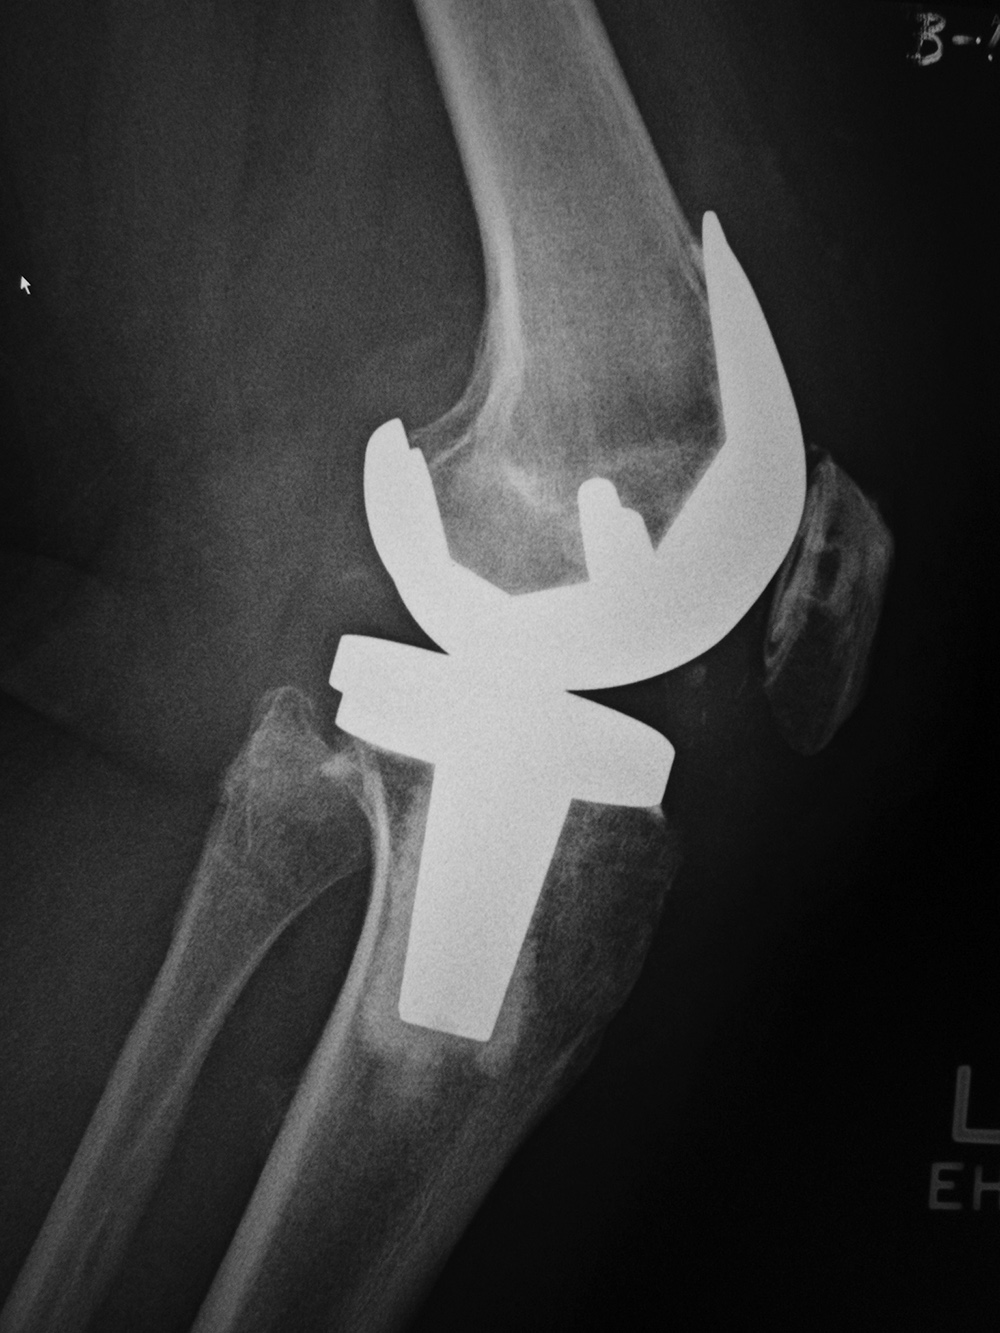

Posterior cruciate substituting total knee prosthesis and patellar resurfacing. |

A posterior-stabilized knee or PCL-substituting knee has removal of the posterior cruciate ligament. This design limits posterior tibial translation in flexion. It contains a posterior cam, deeply dished articular surfaces, plus a third condyle or a central polyethylene post in the posterior middle portion of the tibial insert (figure: cruciate substituting TKA). In flexion this polyethylene post engages a transverse metal cam on the femoral component (Mulcahy, 2013). If the polyethylene post in the tibial insert does not have a metal backing it may not be visible on knee radiography. Usually one can differentiate cruciate-substituting from cruciate-retaining knee arthroplasty

on lateral views. The cruciate-substituting prosthesis often have a larger “box” or thicker femoral component.

| 68 year-old woman treated for severe left knee osteoarthritis |

Note the large distal femoral box. There is a surgical drain in the suprapatellar space. |